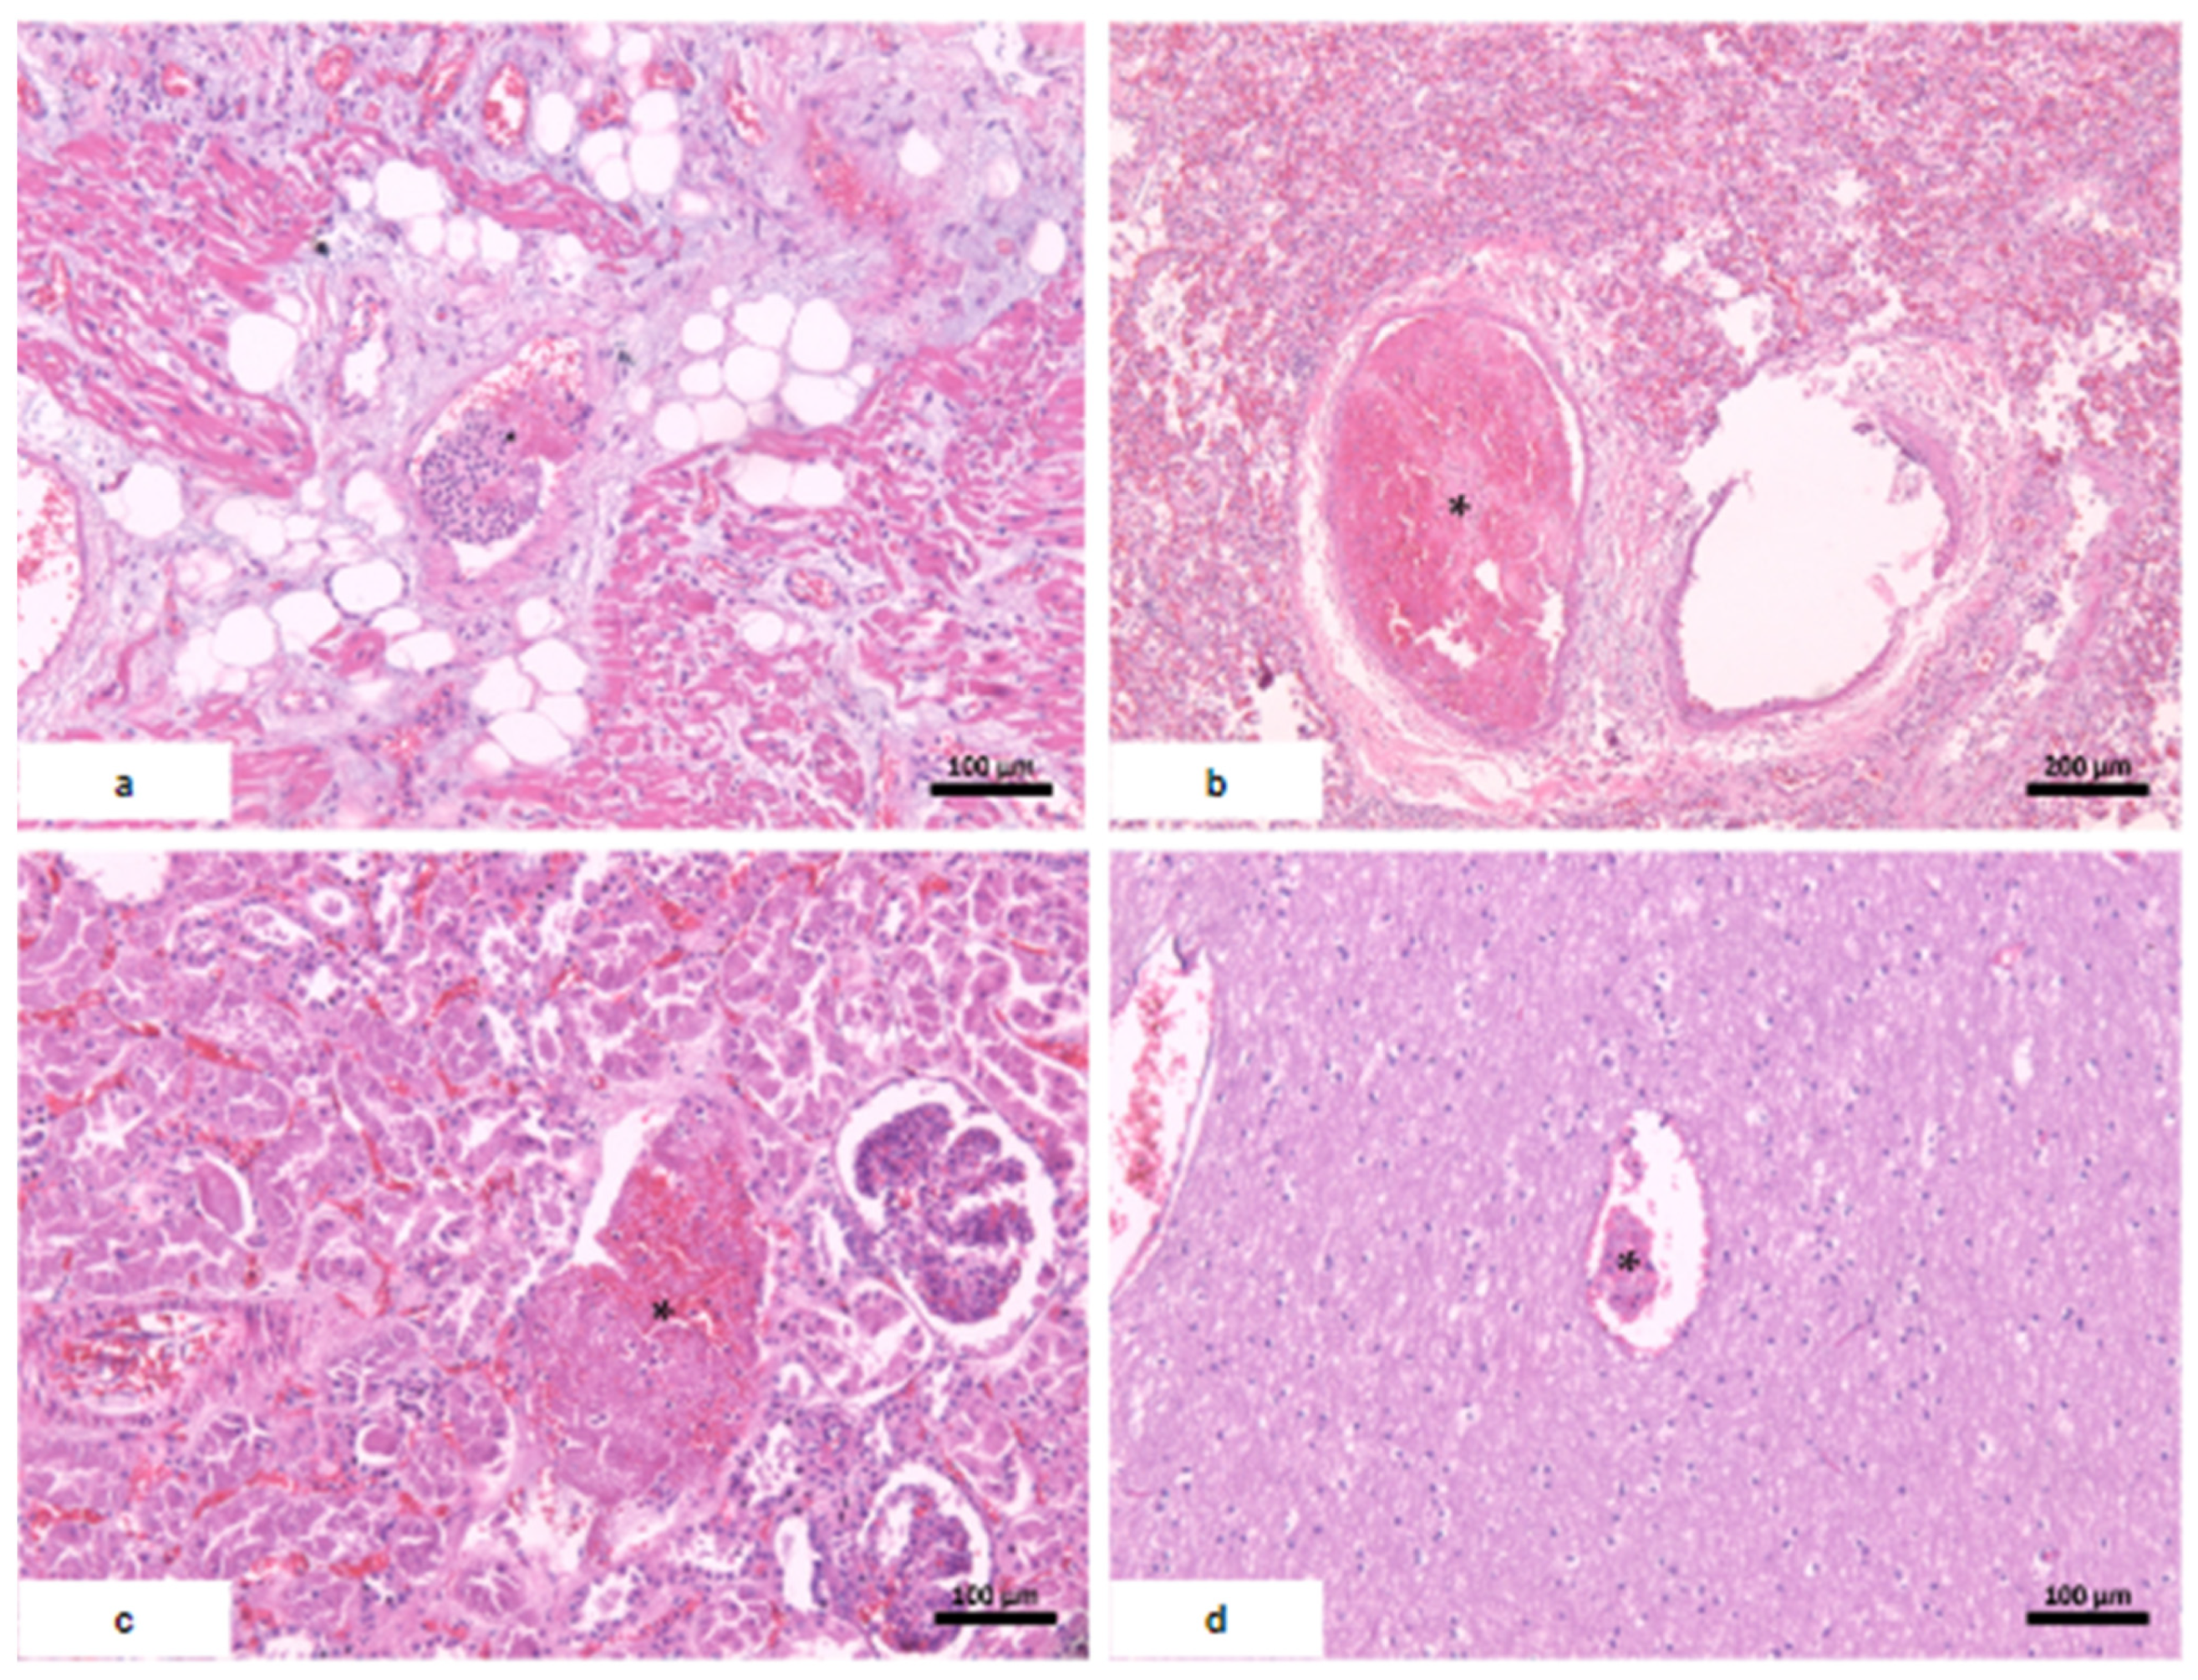

| Macroscopic findings | Edema and tonsil herniation. | Fibrinous perimyocarditis with hemorrhage. Valves unchanged | Edema and congestion. | Moderate steatosis hemorrhagic appearance | Signs of shock. |

| Microscopic findings | Tissue edema. Reactive gliosis. Vascular thromboembolism. | Pericardium: intense deposition of fibrin, red blood cells, and inflammatory cells. Myocardium: interfascicular edema, coagulative myocyte necrosis. Hemorrhage and inflammatory infiltrate rich in macrophages and t-cells. Aschoff’s nodules and/or Anitschkow’s cells: not observed. Endocardium: slight loose fibrosis and inflammatory infiltrate. | Parenchymal hemorrhage. Vascular thromboembolism. Inflammatory infiltrate of lymphocytes, neutrophils, and xanthomatous macrophages. | Hemorrhagic necrosis. Vascular thromboembolism. Microvesicular steatosis. | Acute tubular necrosis. |